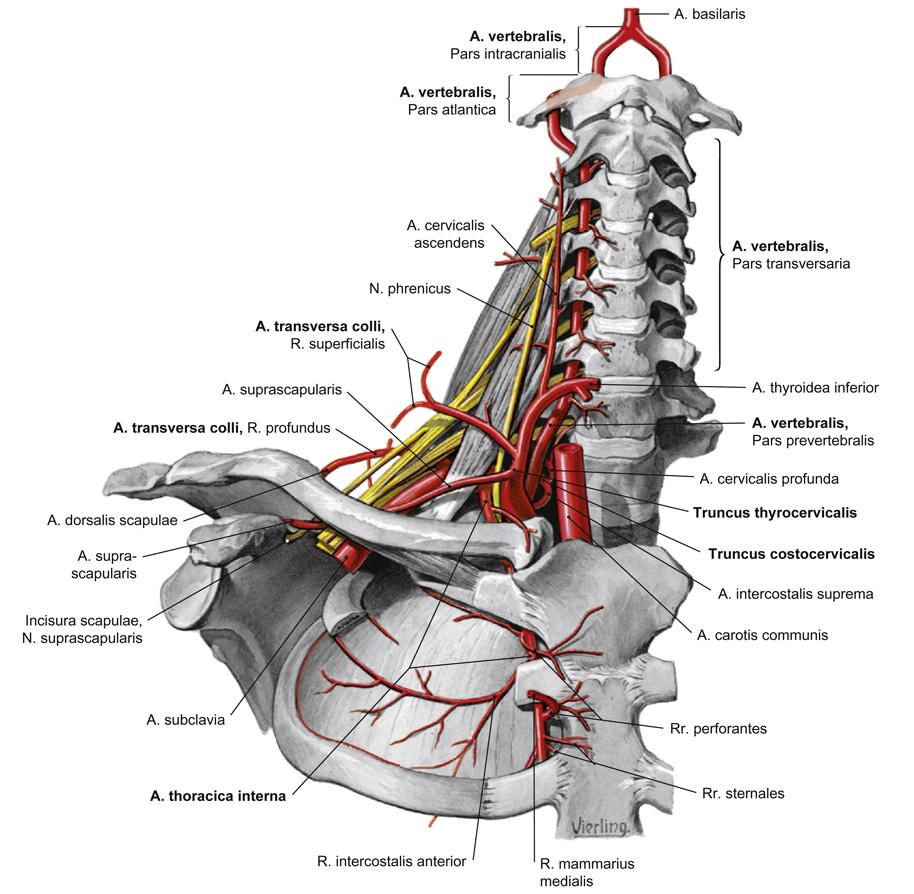

Fig 3.14: a. subclavia - zijtakken

glandula thyroidea = schildklier (groen) rib I tuberculum m. scalenus anterior v subclavia dextra -

truncus brachiocephalicus

a carotis communis (ACC) -

a subclavia dextra

a vertebralis (naar foramen transversarium C6-C2, a. basilaris) -

truncus thyrocervicalis

a thoracica interna = a. mammaria (langs sternum) -

truncus costocervicalis (posterieur)

|

Fig 3.15: a. vertebralis

A C3-C6

proc. transversus foramen transversarium